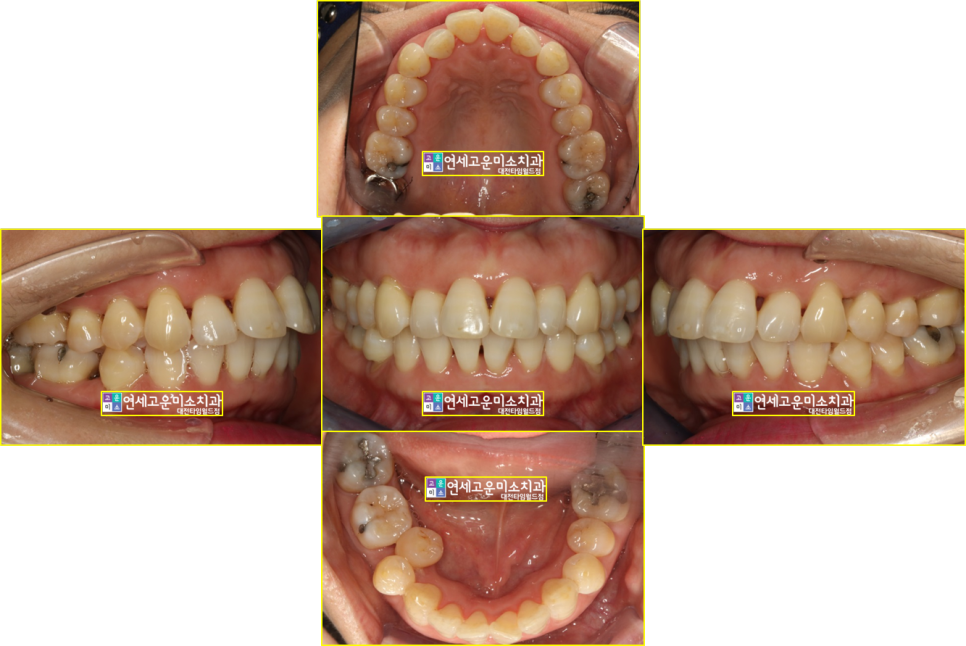

치료 후 입안 사진입니다

덧니도 해결되었고 뻗어 보이던

치아 느낌도 많이 해소가 되었습니다.

치료 전후 엑스레이입니다.

전과 후 치아배열도 좋아졌고

잇몸 건강도 잘 유지되고 있음을 보여줍니다.